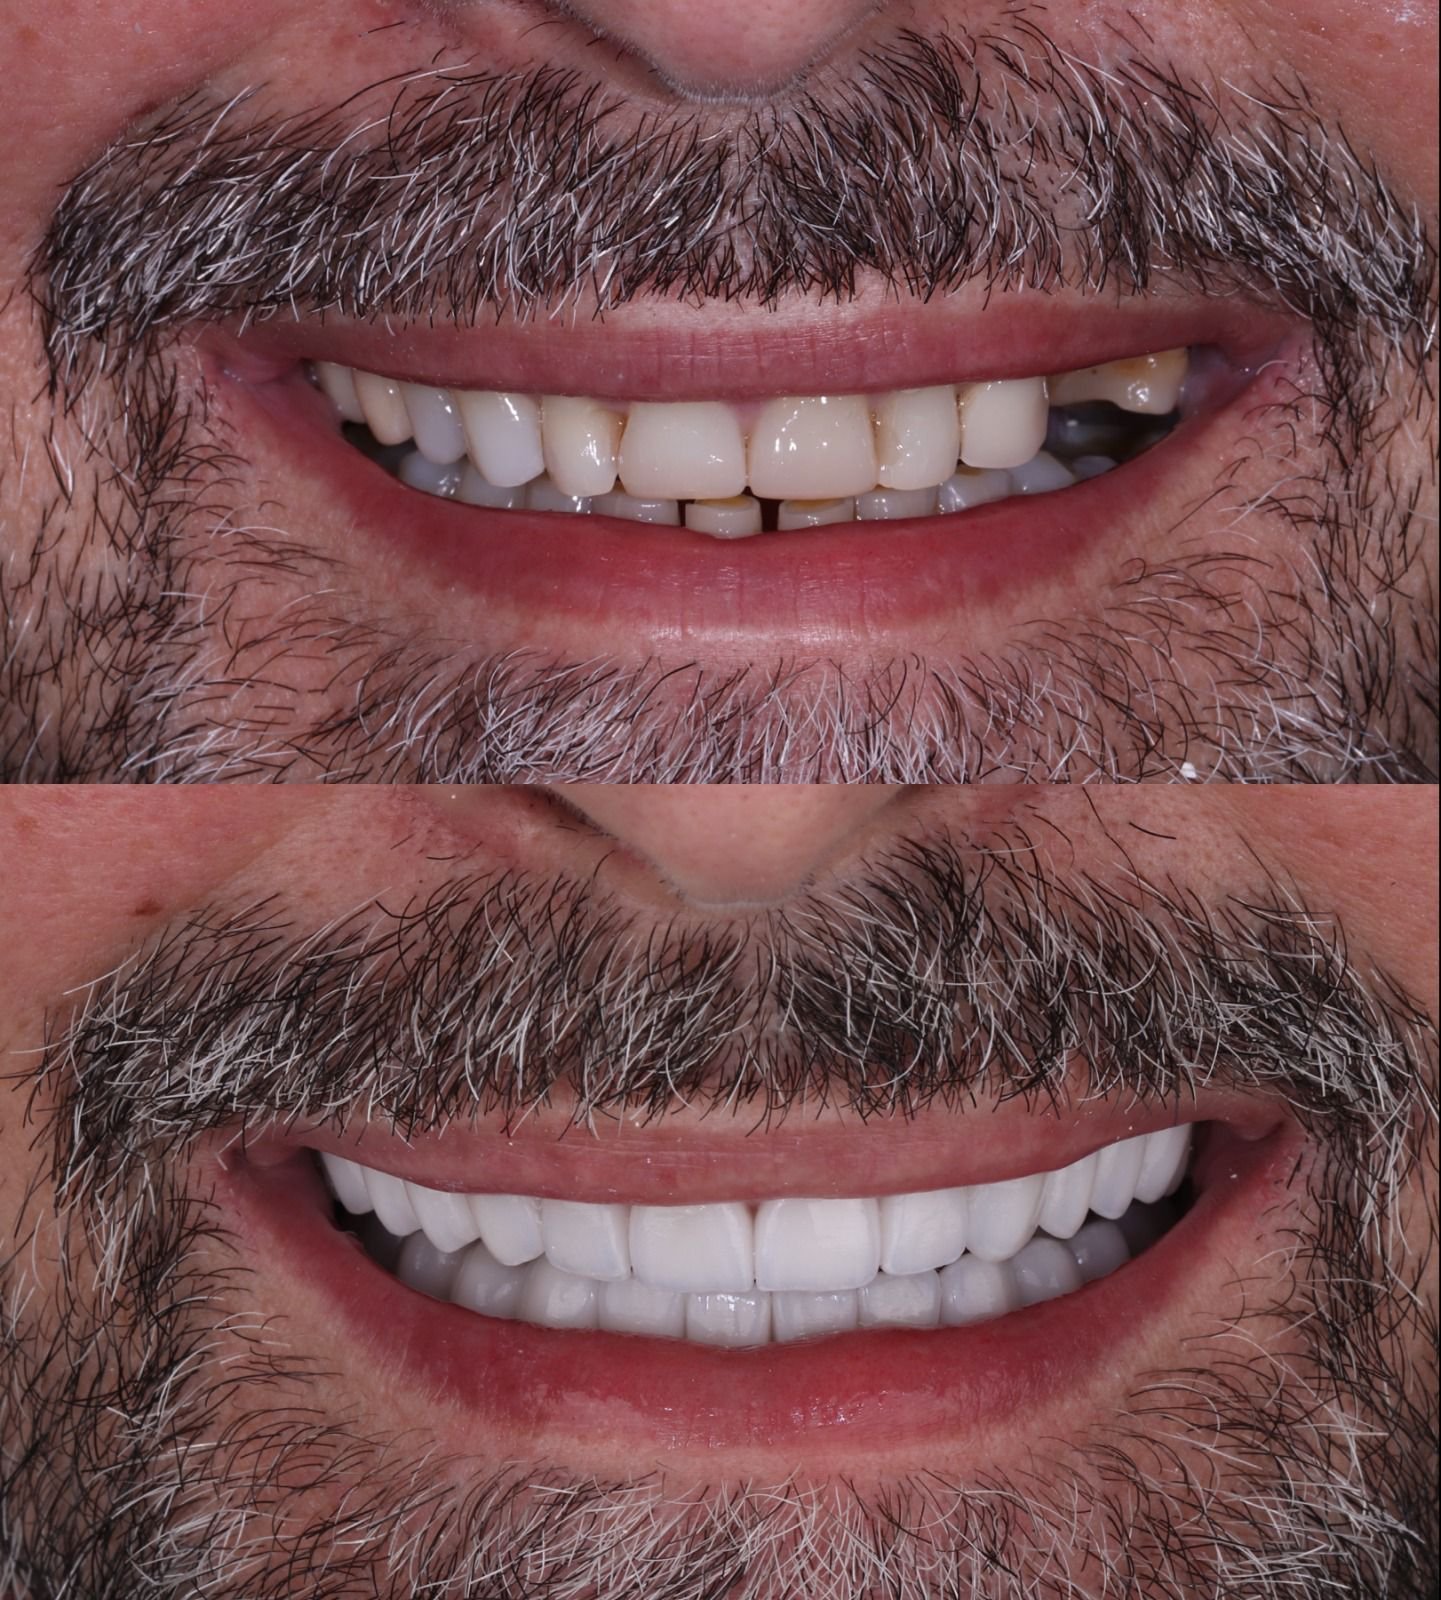

Antes & depois — arraste para comparar

Casos reais tratados na clínica. Deslize o divisor para ver a transformação.

Resultados da clínica